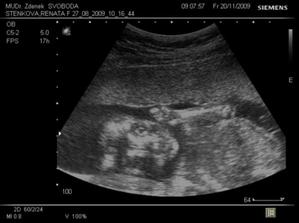

7.10.2009 nás čeká screening v 1. trimestru.*** Tak NT máme zdárně za sebou, nosní kůstka přítomna, NT 1,5 mm, CRL 7 cm i s nožičkama máme 11 cm, mimísek trochu ztěžoval pozorování, kroutil se do všech světových stran, srdíčko a všechny orgány se zdají být v pořádku. Výsledky krve budou až za týden :-/.***22.10.2009 - odběr krve na tripple test atd.., váha 59,2, UTZ bohužel neproběhl, za to jsem si vychutnala poslech srdíčka. A odpoledne konečně výsledky krve z NT - máme je v pořádku, riziko 1:12.900, huráá. Další kontrola na gyn. 20.11. - bude UTZ s vyloučením VV plodu a pak ve 21. týdnu USG srdce plodu u dr. Rušavé.***26.10.vystavena neschopenka, tripple test o.k. 🙂.***20.11. tak velký utz je v pořádku a mamka na vlastní oči viděla pindíka 🙂. Máme 356 g. Já váha 59,6. Další kontrola 16.12.***10.12.vyšetření srdíčka na dětské kardiologii, máme vše o.k. 🙂***14.12. 3/4D utz na genetice, vše je v pořádku, máme už 590 g a 30 cm, malej si dal hodně záležet na utajení vzhledu obličejíčku 😀, ale na DVD jsem ho v maličkej momentík nachytala.***5.1.2010 - test na cukrovku***13.1.2010 - kontrola na gyn., váha 64,5, na tvrdnutí břicha nasazeno magnézko polykací, hrdlo stále uzavřeno naštěstí..ale bohužel výsledky na cukrovku - pozitivní, hodnota na lačno 4,8, po 2 hod. 8,1, takže se musíme objednat na diabetologii :-/.***15.1. návštěva diabetologie, dostala jsem glukometr a 3 dny v týdnu si budu měřit, za 14 dní kontrola***28.1.utz ve 30.týdnu, vše o.k., máme 1761 g, hlavičkou dolů. ***17.2. kontrola, odběr krve, váha 67,2, další kontrola 1.3.***1.3. první natáčení na monitor, vše o.k., váha 67,8. Další kontrola 10.3.***10.3. monitor o.k., chvíli malej chrupkal, ale za chvíli si zas jel svoje tempíčko🙂, váha 68,8. Dnes mi byla ukončena PN a začala MD. Další kontrola 18.3.***monitor o.k., váha 70,2, začíná se projevovat zadržování vody v těle - už od rána nateklý kotníky a ruce, snubák už radši nenosim. Další kontrola 25.3.***25.3. na monitoru na křivce stahů první obloučky, něco se začíná dít?? Váha zase 70,2. Další kontrola 1.4.***Monitor v pořádku, váha 71,3. Další kontrola už bude v porodnici dne 7.4. ráno, tašku mít radši s sebou :-O...